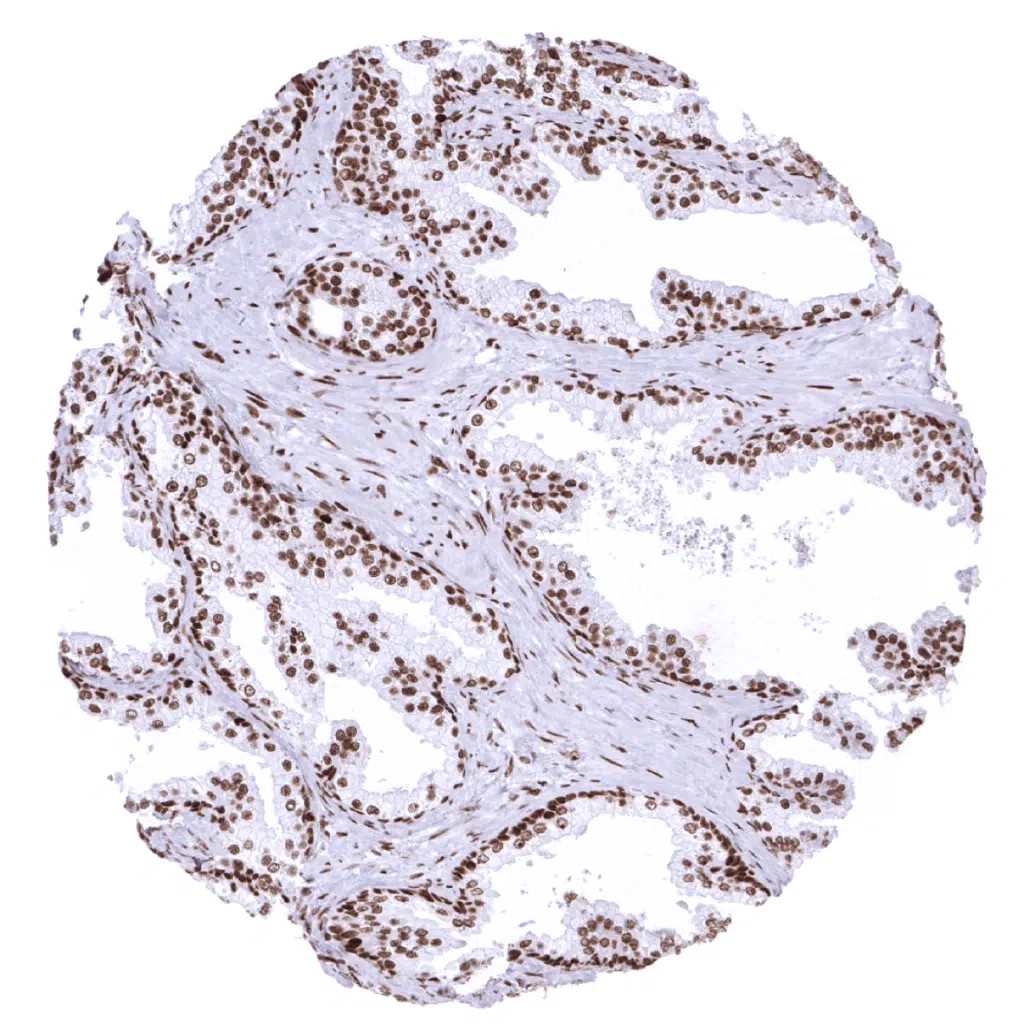

Rectum, mucosa – In the colon (and rectum) epithelium, the MSH2 staining intensity decreases from the bottom to the top of the crypts.